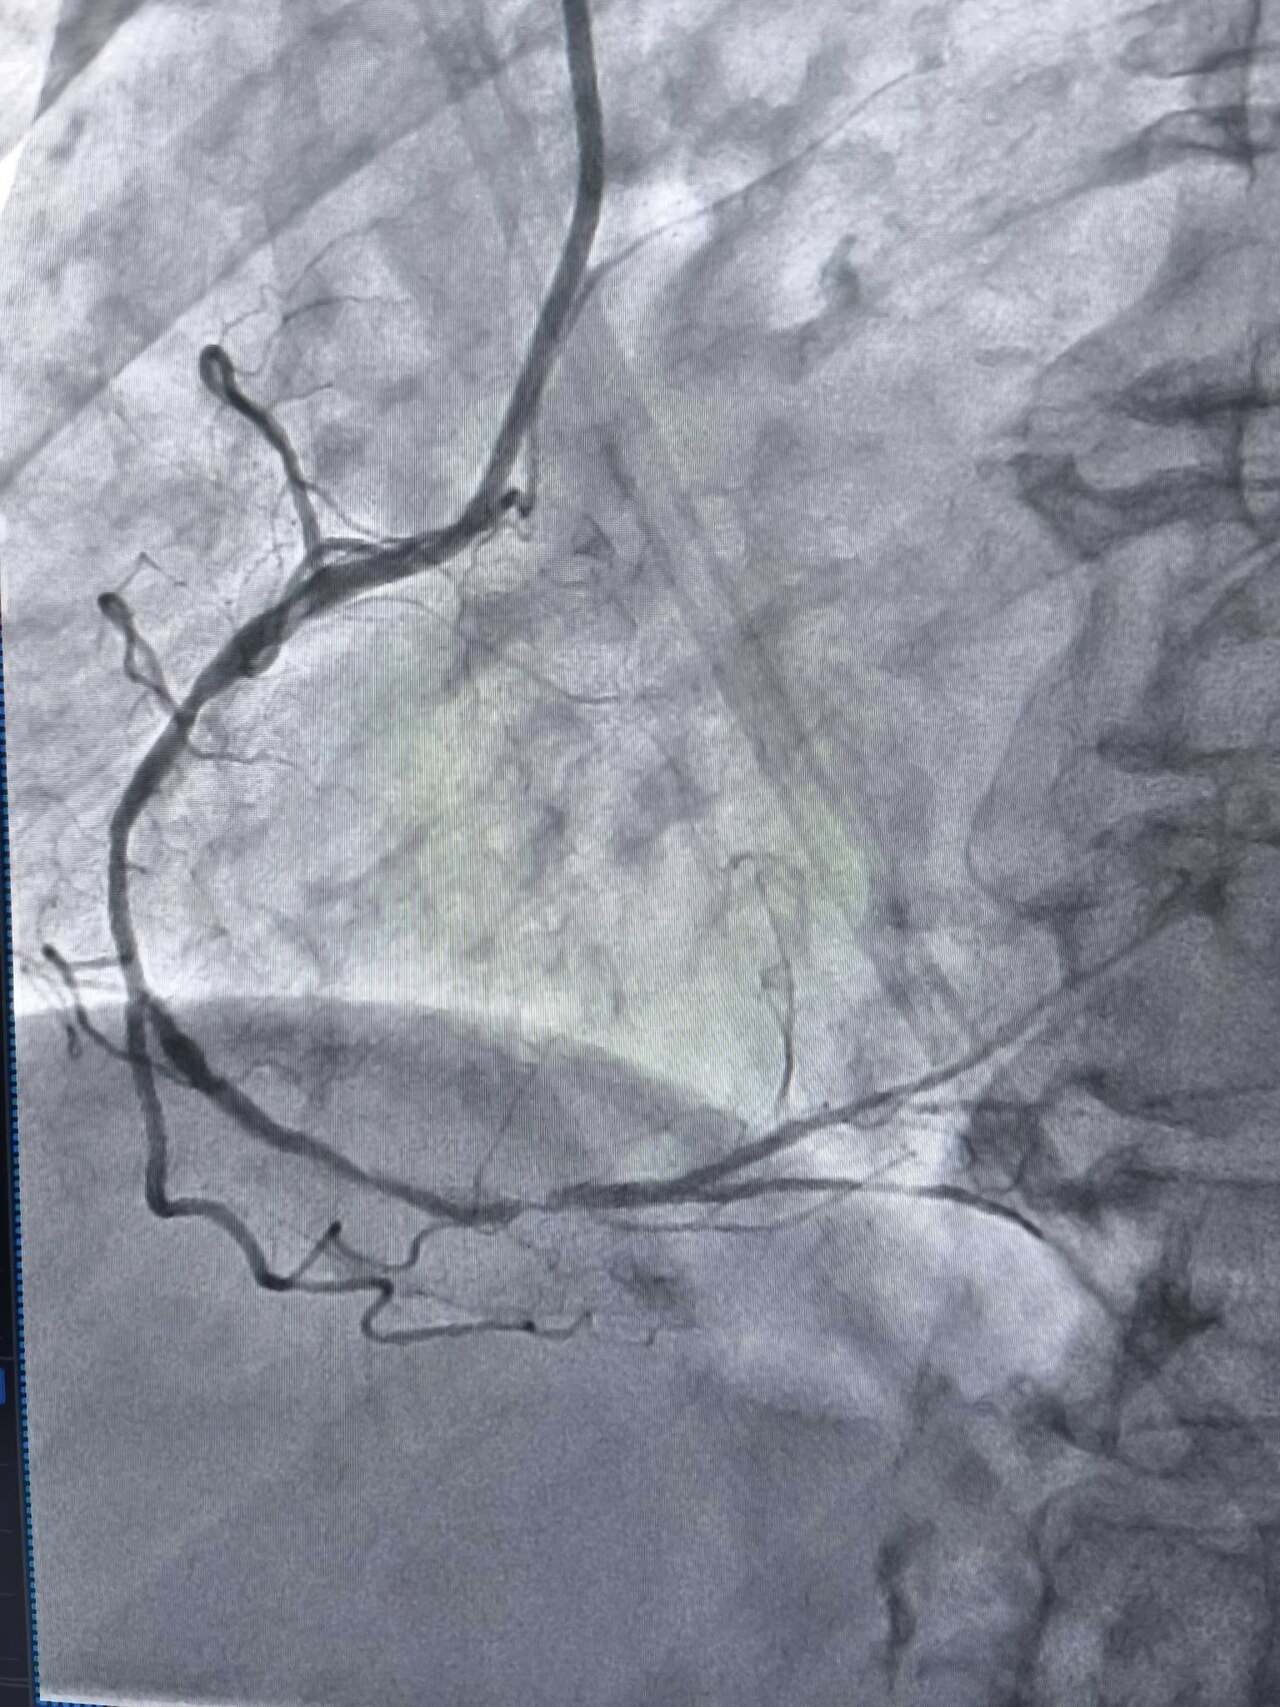

Високотехнологічну процедуру – ротаційну атеректомію вперше на Тернопільщині провели в обласній клінічній лікарні. Про це повідомили у пресслужбі лікарні.

Йдеться про складне втручання, яке застосовується у випадках вираженого кальцинозу коронарних артерій, коли стандартні методи не дають результату.

У таких ситуаціях на допомогу приходить ротаблятор – спеціальний пристрій із буром, покритим діамантовим напиленням. Він дозволяє «модифікувати» кальциновану атеросклеротичну бляшку, фактично шліфуючи її та відновлюючи можливість для подальшого стентування судини. Саме таким методом лікарям вдалося ліквідувати перешкоду в артерії та успішно імплантувати стенти.

Це втручання стало важливим кроком для нашої лікарні та всієї області. Ротаційна атеректомія застосовується у найскладніших випадках кальцинованих уражень коронарних артерій, коли стандартна ангіопластика неефективна. Виконання такої процедури означає, що пацієнти Тернопільщини можуть отримати сучасну високоспеціалізовану допомогу без необхідності їхати в інші регіони, – наголосив Богдан Маслій.

Фото Тернопільської обласної клінічної лікарні